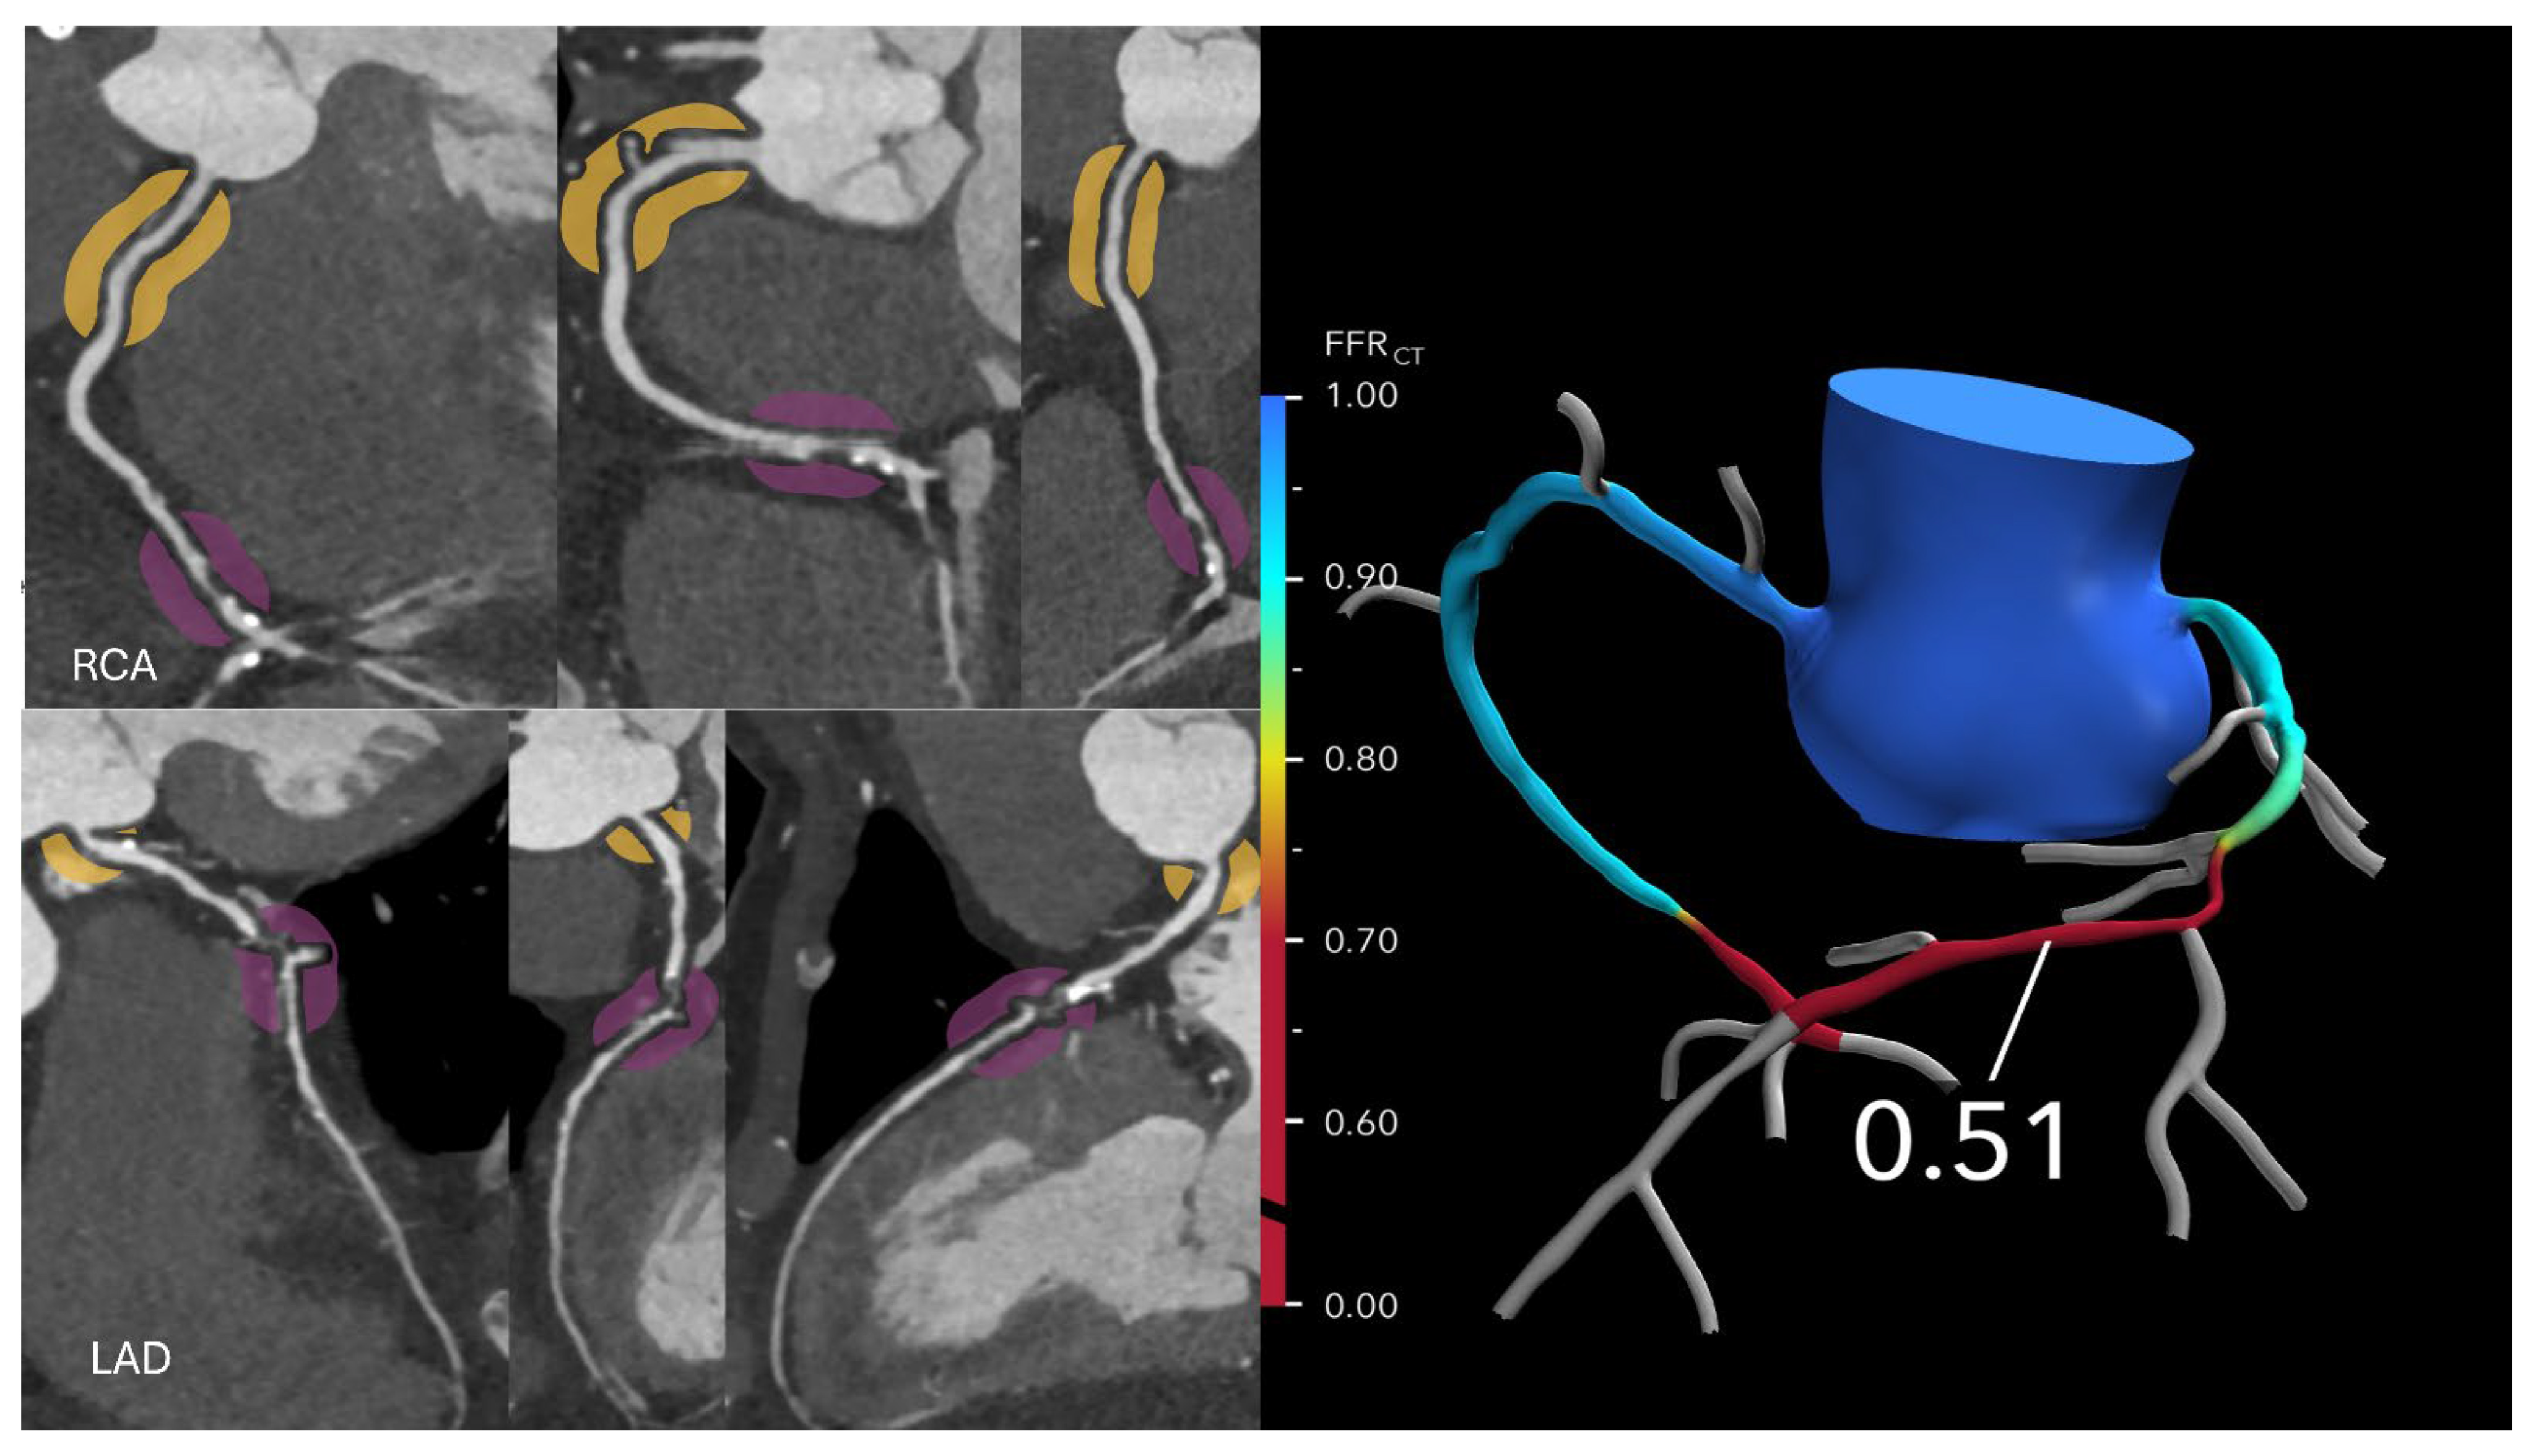

Figure 3. Optimizing treatment decisions with FFR-CT: (Left): A curved multiplanar reformatted coronary CTA image in a 64-year-old man with stable chest pain reveals severe stenoses in the mid left anterior descending (LAD) artery and distal right coronary artery. (Right): The corresponding FFR-CT image shows a value of 0.51 measured 2 cm distal to the lesion, indicating severely reduced flow. Based on these findings, the patient proceeded to invasive coronary angiography, followed by intervention. Please refer to Figure 4’s caption for the degree of stenosis in relation to different colors. Reprinted with permission under open access from Kasaeian et al. [6].

Kasaeian et al. reviewed the clinical applications of FFR-CT in coronary artery disease [6]. FFR-CT has been increasingly reported in the literature to yield improved accuracy in guiding patient management compared to standard coronary CT angiography (CTA). Real-world evidence of using FFR-CT in clinical practice has been validated by a number of multicenter trials proving that FFR-CT serves as a gatekeeper to invasive coronary angiography by reducing a significant number of unnecessary invasive procedures (Figure 2 and Figure 3). FFR-CT is associated with significantly lower all-cause mortality, so it can guide confidential clinical decision-making. Judicious use of FFR-CT to guide coronary CTA interpretation was discussed alongside distal-to-lesion FFR-CT measurement, showing improved concordance with invasive FFR, hence further enhancing diagnostic precision. In this study, the limitations of FFR-CT are highlighted, along with the impact of high-quality coronary CTA image acquisition and coronary calcium scores on FFR-CT performance. Future potential applications of FFR-CT, such as its implementation in the evaluation of coronary artery anomalies (Figure 4) and plaque characterization, are also reviewed. These authors also reviewed the role of FFR-CT as a reliable tool to plan percutaneous coronary intervention (PCI) and identify suitable patients undergoing coronary artery bypass grafting. Finally, they summarized the role of FFR-CT combined with risk stratification as a gatekeeper to the catheterization lab to reduce unnecessary invasive procedures without comprising clinical outcomes.